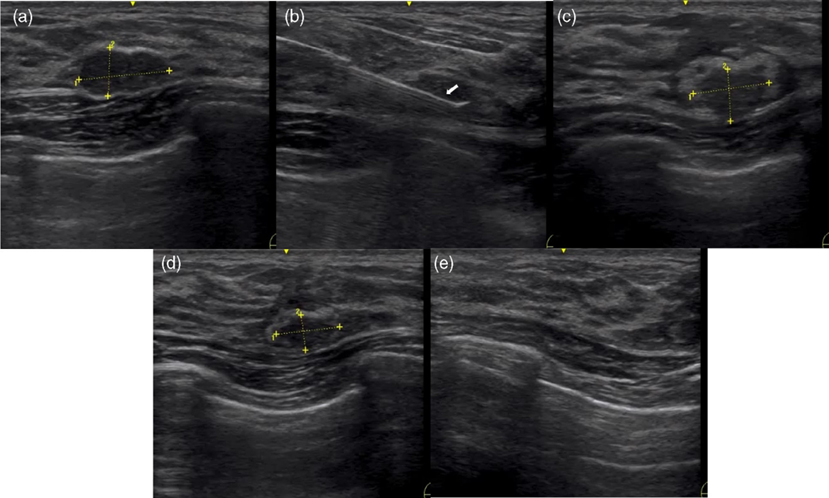

典型乳腺良性病變消融前后超聲變化如Fig1所示

Fig1 微波消融前后乳腺良性病變的代表性超聲圖像。(a)MWA前超聲下病變最大直徑12.7 mm。(b) MWA期間超聲掃描。箭頭所示的為微波消融針。(c)消融后3個月,超聲掃描顯示病變直徑為10.7mm。(d)消融后6個月,超聲掃描顯示病變直徑為8.9 mm。(e)12個月時超聲掃描顯示完全消融。

MWA消融12個月,病變體積從MWA前的529.2 (64.3-6378.75) mm3減小到66.2 (6.30-2598.75)mm3,平均VRR為87.5% (p < 0.01)。最長直徑≤20mm的病變,消融后12個月的VRR達到100%。Fig2顯示了MWA后12個月未完全吸收病變的體積變化。